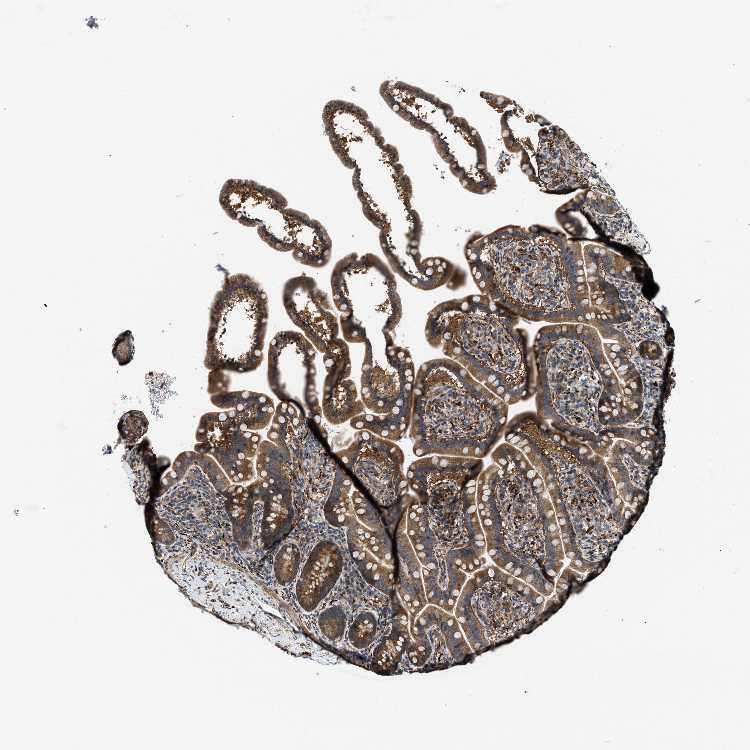

ZNF599